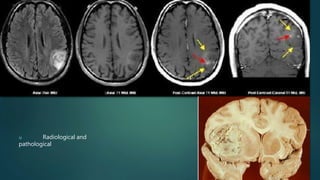

u Radiological and

pathological